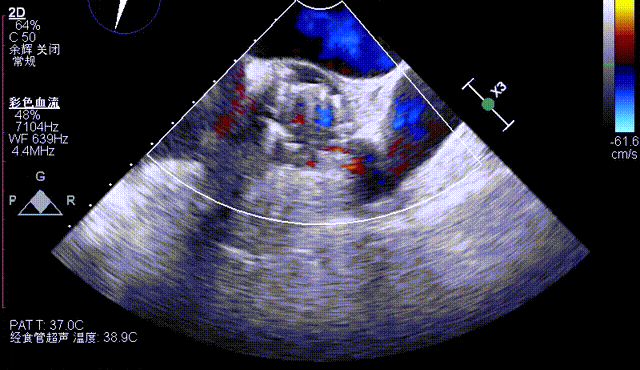

术后即刻评估

术后即刻TEE示主动面瓣膜最大峰值血流速为1.1m/s,平均跨瓣压差为2mmHg,少量瓣周漏。